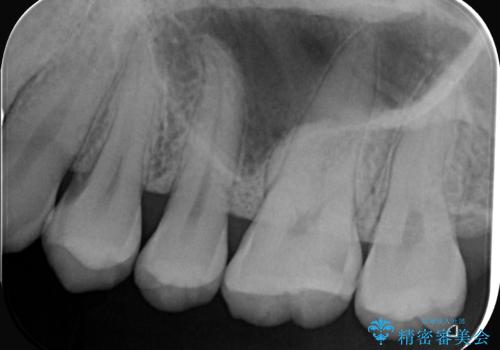

- 主訴:舌で触ったら歯に穴が空いていた。しみたりはしていない。

左上6番目の歯の噛む面に穴が空いていました。穴自体は小さいものでしたが、歯の中で虫歯が広がっていることが確認でき、虫歯の大きさを考慮しインレーでのやり替えとなりました。

咬合面に穴が空き、歯の中でう蝕が広がっていました。この歯が過去に咬合面う蝕を経験しCR修復を受けていること、今回歯質とCRの境目からの二次う蝕になっていることを説明し、適合や材料安定性の良いセラミックインレーでのやり替えとなりました。